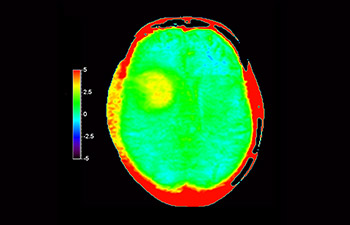

Neurologische Leiden stellen eine schwere Belastung dar. Philips hat es sich zum Ziel gesetzt, hochwertigste Neuro-Bildgebung zu ermöglichen – für eindeutige Diagnosen und eine schnelle Therapie. Wenngleich die MRT heutzutage den Goldstandard in der neuroradiologischen onkologischen Bildgebung darstellt, kann die Genauigkeit beim Tumor-Grading und den Nachsorgeuntersuchungen noch weiter verbessert werden. 3D APT (Amide Proton Transfer) ist eine einzigartige, kontrastmittelfreie Methode zur MR-Tomographie des Gehirns, die den Bedarf nach einer sichereren Diagnose in der Neuroonkologie erfüllt. 3D APT nutzt das Vorhandensein von endogenen zellulären Proteinen zur Erzeugung eines MR-Signals, das direkt mit der Zellproliferation, einem Marker für Tumoraktivität, korreliert. 3D APT kann geschulte medizinische Fachkräfte dabei unterstützen, gering differenzierte von hochdifferenzierten Gliomen und Tumorverhalten von Behandlungseffekt zu unterscheiden1.